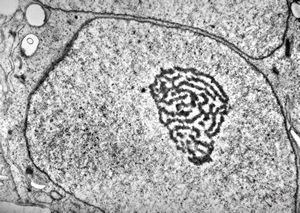

F,50y. | progressive multifocal leukoencephalopathy- viral particles in a glial cell